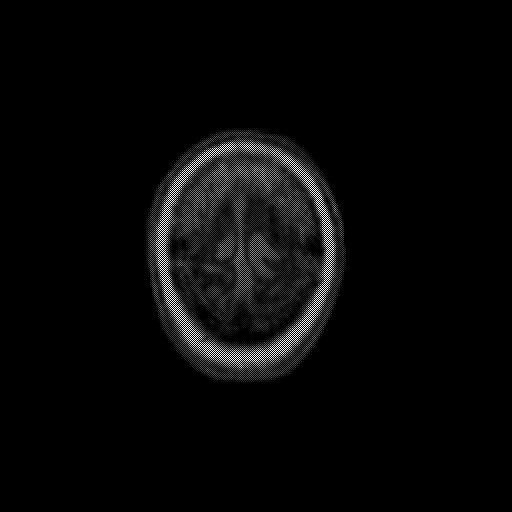

overlay: Slice 49

Slice 49

MRCBFCBF with

T1PDT2T1PDT2